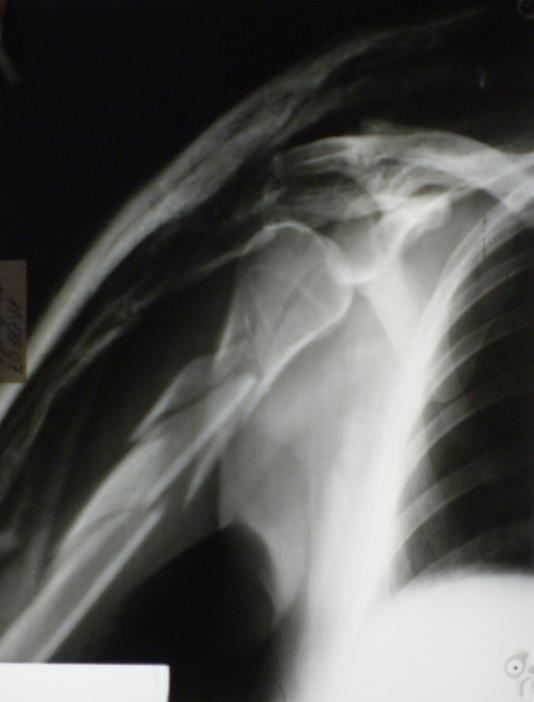

[Ortho] Многооскольчатый перелом плечевой кости в В/3

Немножко переделал повязку с отведением, подправил, вот что получилось.

Перелом внутрисуставной, Вы уверены на счет Сармиенто? На первичном

снимке не видно было перелома головки.